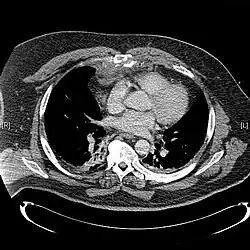

CT scan showing a comminuted sternal fracture.[12]

X-rays of the chest are taken in people with chest trauma and symptoms of sternal fractures, and these may be followed by CT scanning.[13] Since X-rays taken from the front may miss the injury, they are taken from the side as well.[14]